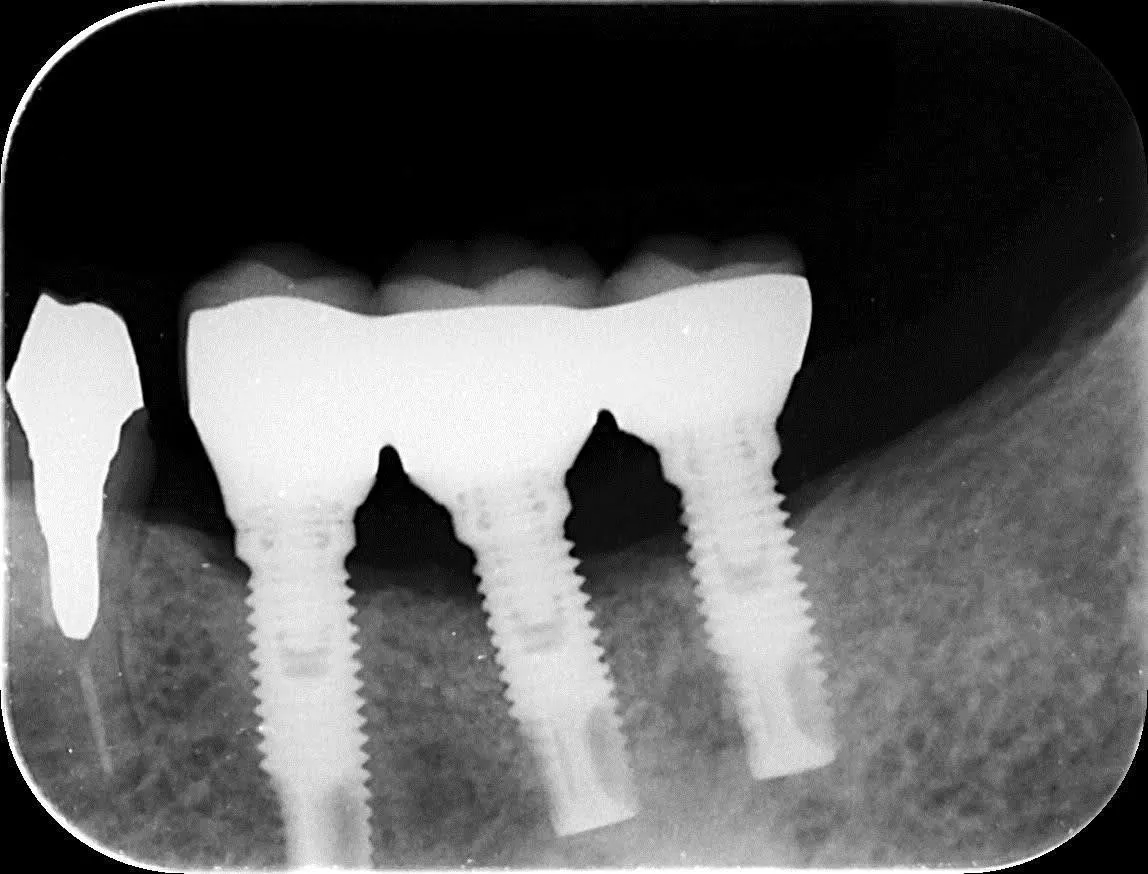

―過去に他院で埋入したインプラントのフォローアップ

炎症を起こして真ん中のインプラント周囲の骨がかなり溶けています。

冠も適合が悪く隙間ができています。

- 治療費(税込): 40万

- 治療期間: 6ヶ月

- 治療回数: 8回

- 副作用(デメリット): 保険が使えない

外科処置で骨の再生を促し、土台と冠を作り直しました。

真ん中のインプラント周囲の骨が見事に再生しています。

当院では、過去に治療した後の不具合も対応しています。遠慮なくご相談ください。